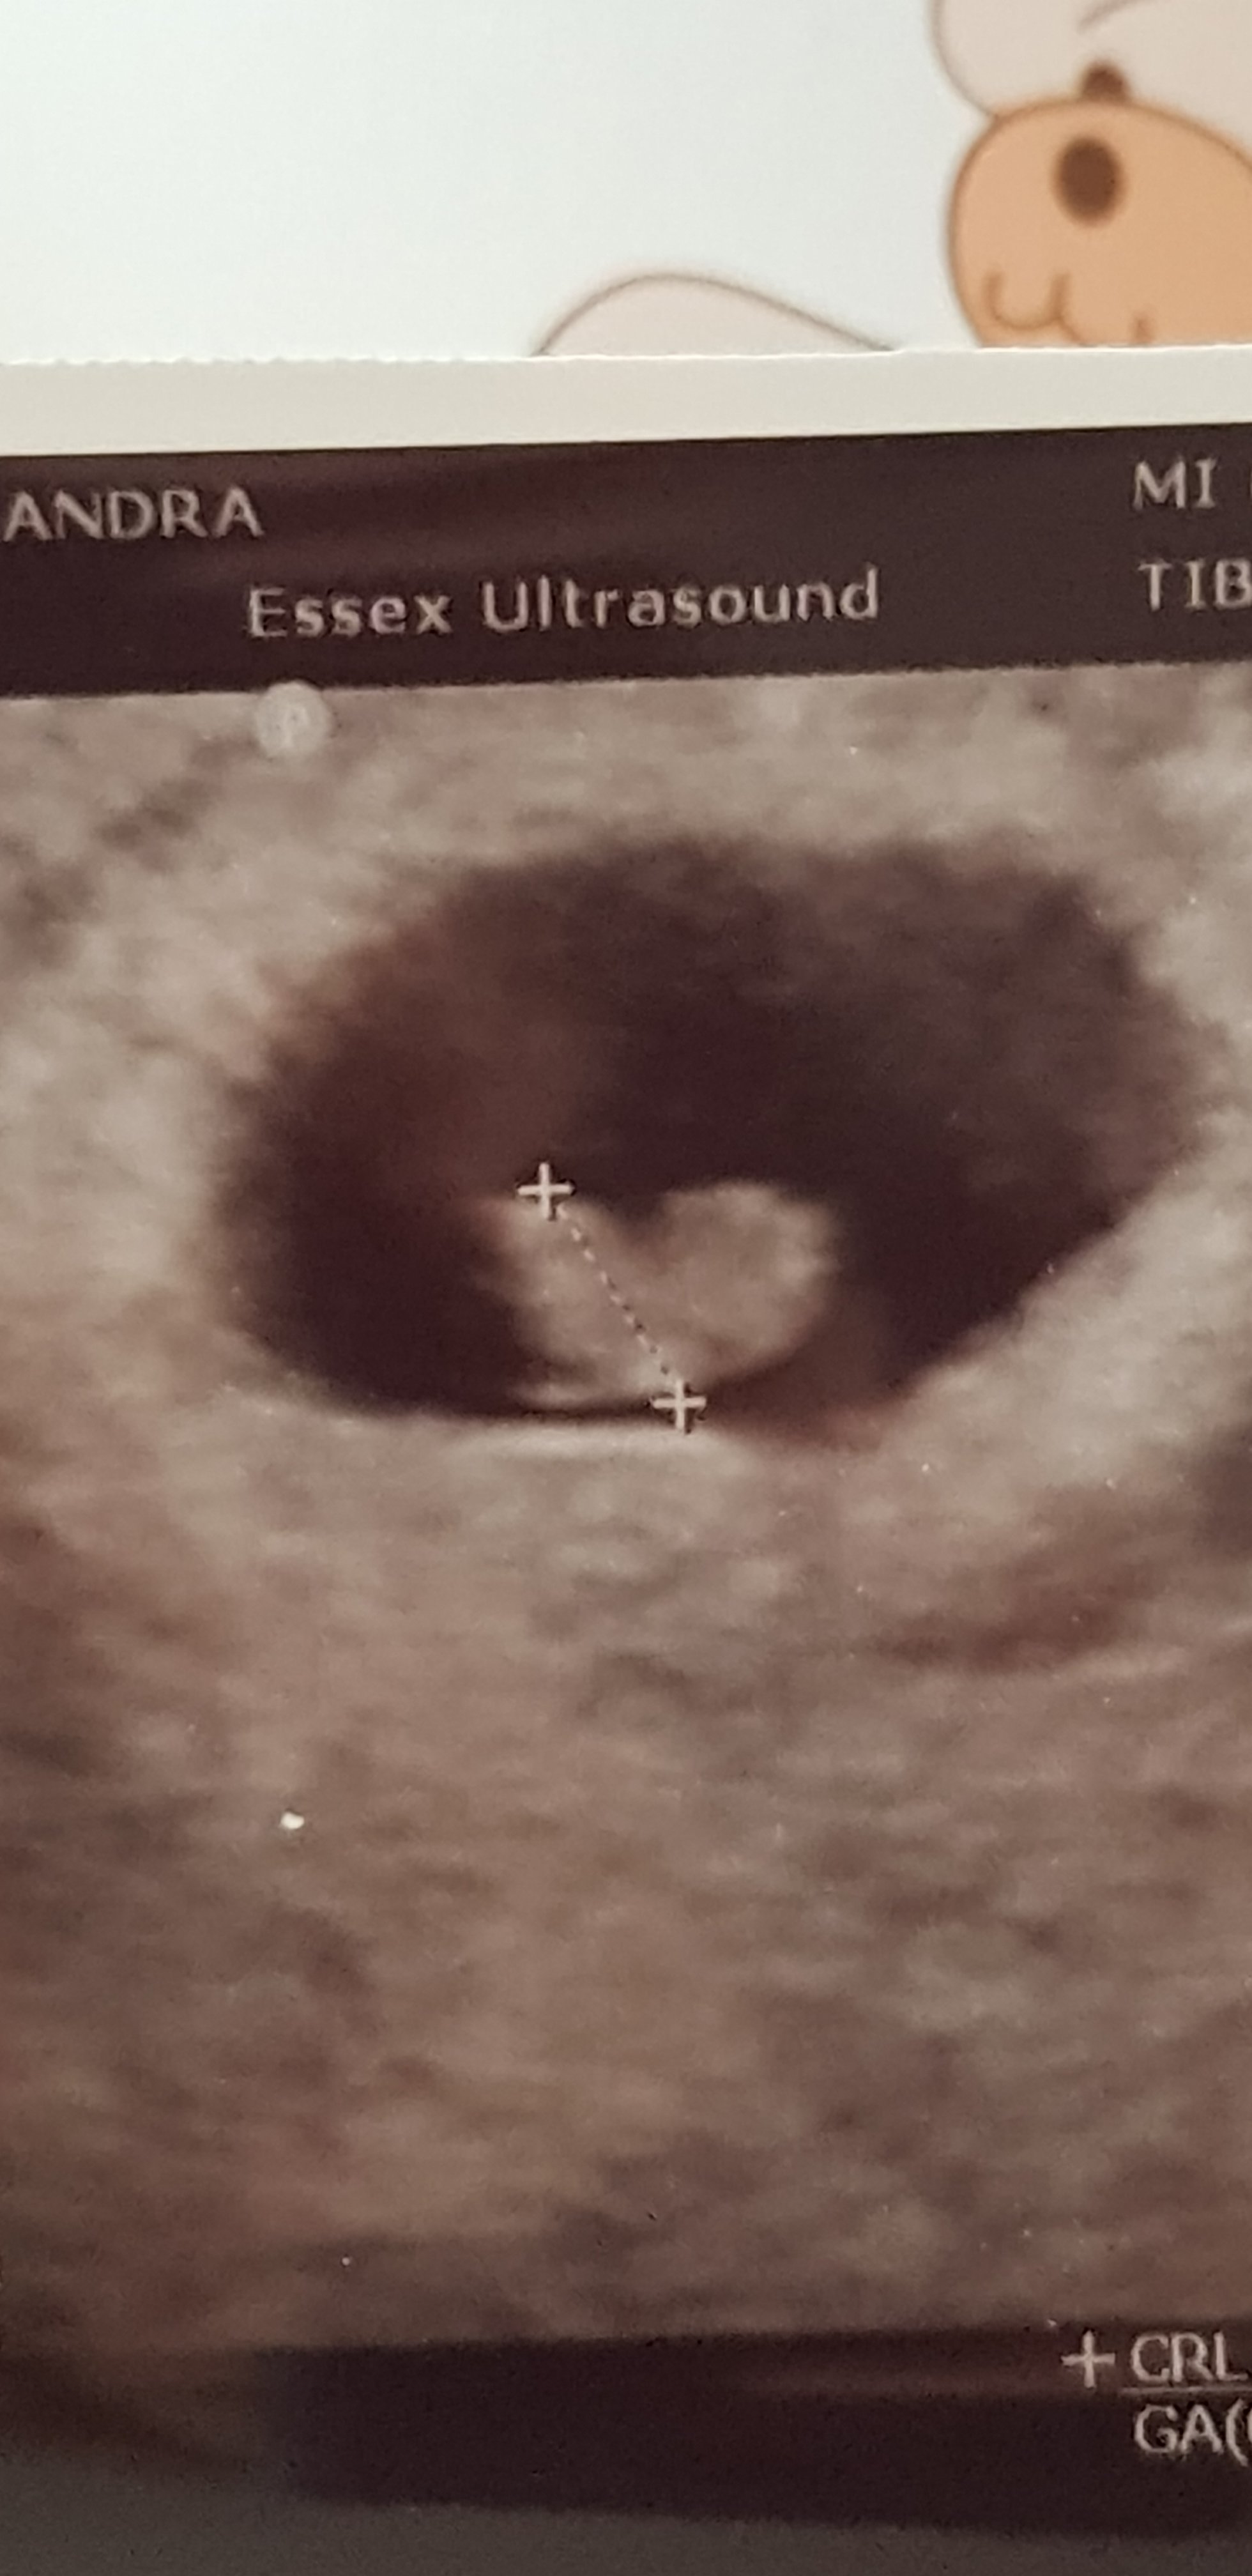

Gratulacje kochana. A ktory tydzień wychodzi z om?Przedstawiam moja kropke z bijacym serduszkiem,dawno juz sie tak nie ucieszylam,z pomiarow dziecka wyszlo ze to dopiero 6tyd2dni.wszystko sie miesci w normie rozmiarowej,serce ladnie bije,juz jestem spokojniejszaZobacz załącznik 947433

Przedstawiam moja kropke z bijacym serduszkiem,dawno juz sie tak nie ucieszylam,z pomiarow dziecka wyszlo ze to dopiero 6tyd2dni.wszystko sie miesci w normie rozmiarowej,serce ladnie bije,juz jestem spokojniejszaZobacz załącznik 947433